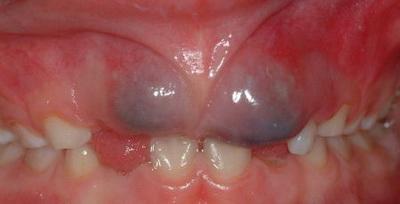

- Гематома — отёк округлой формы, затрагивающий внутреннюю поверхность щеки (в некоторых случаях напоминает флюс), иногда бывает в виде припухлости тёмного синюшного цвета (чаще всего в верхней части десны). Кровь скапливается (в результате кровоизлияния) вокруг зуба или в корне. Слизистая при этом увеличивается в объёме, больной чувствует дискомфорт и не может до конца сомкнуть челюсть. Возможные причины: травмы десны, последствия удаления или пломбировки зуба, проблемы со свёртываемостью крови.

Фото 1. Шишка на верхней десне у ребенка, при прорезывании молочных зубов.